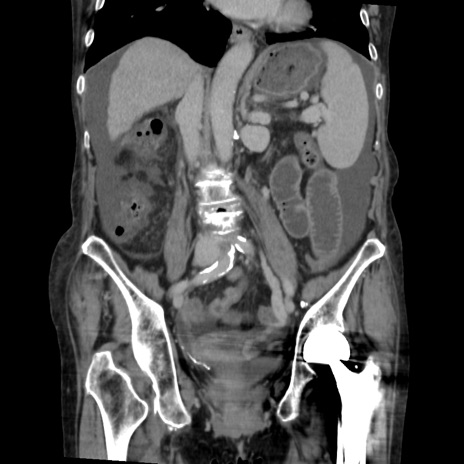

症例31(冠状断像)